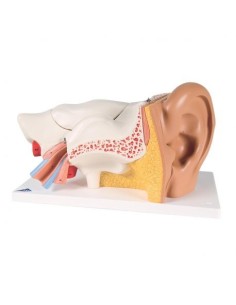

3B Modèle anatomique scientifique des osselets de l'oreille, E13

3B Modèle anatomique scientifique des osselets de l'oreille, 20 fois agrandi comme un os.